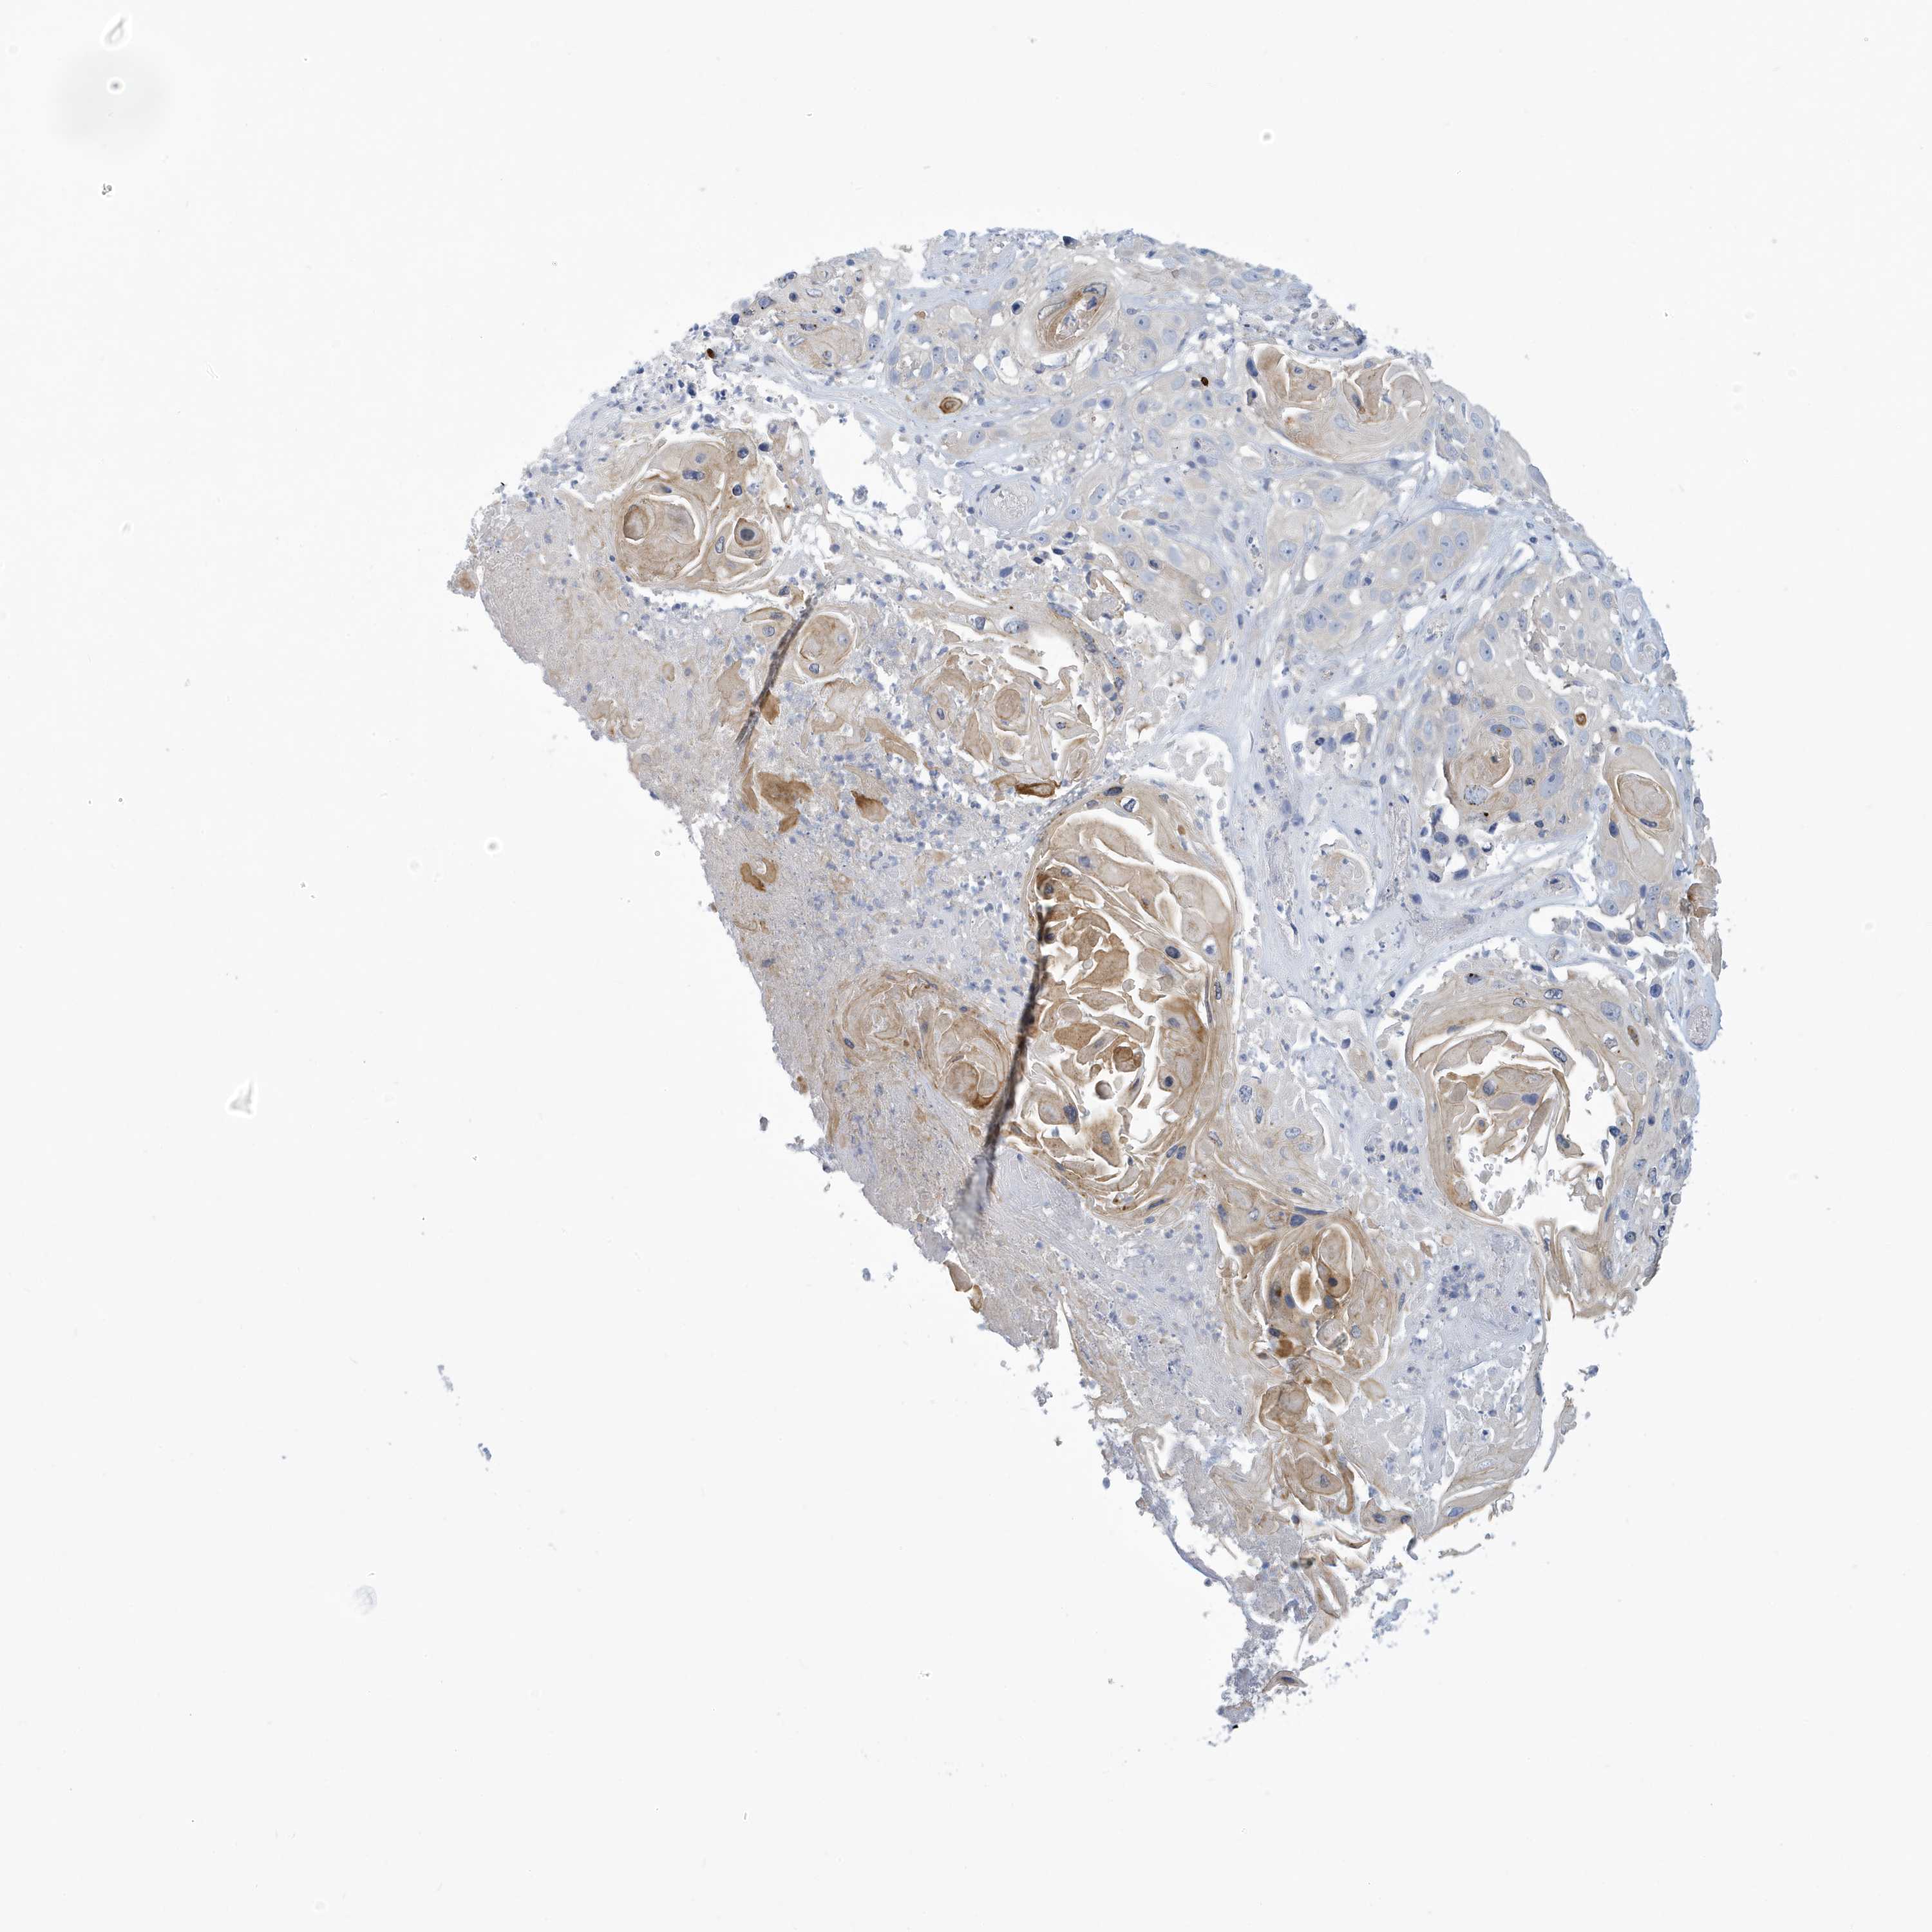

Basal cell and squamous cell cancer

SKIN CANCER - Protein expressioni

A mouse-over function shows sample information and annotation data. Click on an image to view it in a full screen mode. Samples can be filtered based on level of antibody staining by selecting one or several of the following categories: high, medium, low and not detected. The assay and annotation is described here.

Each image is clickable and will lead to virtual microscopy that enables deeper exploration of all samples and also displays staining intensity scores, fraction scores and subcellular localization as well as patient and tissue information for each sample.

Antibody HPA030968

Staining

High

Medium

Low

Not detected

Intensity

Strong

Moderate

Weak

Negative

Quantity

>75%

75%-25%

<25%

None

Location

Nuclear

Cytoplasmic/membranous

Cytoplasmic/membranous,nuclear

Basal cell carcinoma